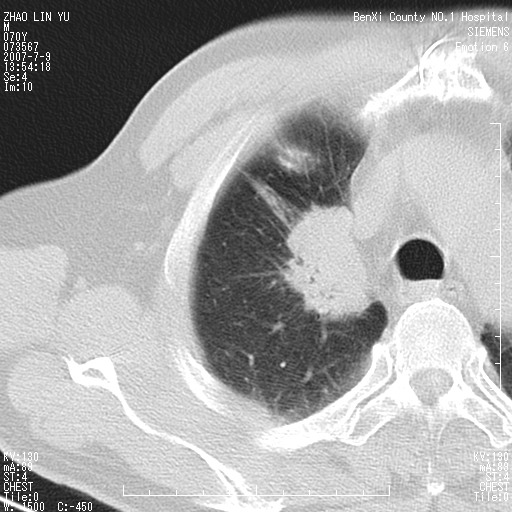

以下是引用王靖旗在2007-7-10 17:12:00的发言:[br] 男、70、咳嗽两个月,半年前换瓣手术,胸片未见异常,于昨天行x片发现右肺上野大片影,行ct扫描,这里是减薄图像,余肺正常。明天晚上会有增强扫描片,到时我会上传。[br][br] 冠状位请大家细看,应该是有意义的,[br][br] 请大家先看平扫发表意见。[br][br]

[br]冠状面[br]

以下是引用zhangzhongshou在2007-7-10 21:43:00的发言:[br]右肺上叶周围型肺癌,以孤立型细支气管肺泡癌可能性大。